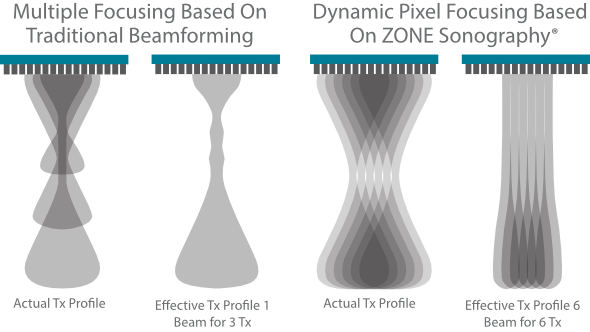

Since the company was founded, Mindray has been continuously exploring new ways to improve diagnostic confidence. Powered by the most revolutionary ZONE Sonography? Technology, Resona 7ŌĆÖs new ZST+ platform brings ultrasound image quality to a higher level by zone acquisition and channel data processing.